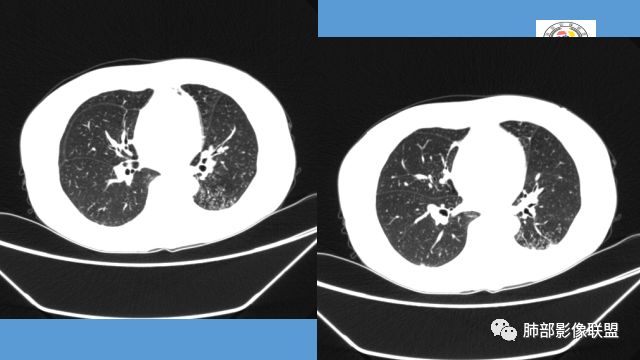

树芽征、小叶间隔增厚,淋巴结, 内部血管走形自然

分析:支气管粘液栓、支气管堵塞处萎缩、钙化,支气管通畅处部分扩张,树芽征——提示结核。

看这些钙化

前壁不厚,附近钙化灶太多,所以觉得结核一定要考虑,加上树芽征,就更支持。

支气管壁软骨存在且连续,没有被破坏掉,支气管壁局部通畅,提示支气管壁没破坏,那么近端支气管癌肿不考虑。远端有树丫征,病灶周围很多钙化,所以结核一定有。

1.双肺多发病灶,结节影、树丫影,边缘分布……病灶符合继发性肺结核。